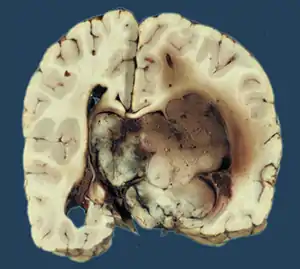

- Micrograph of a choroid plexus papilloma. H&E stain.

- Plexuspapillom Detail

- Plexuspapillom Overview